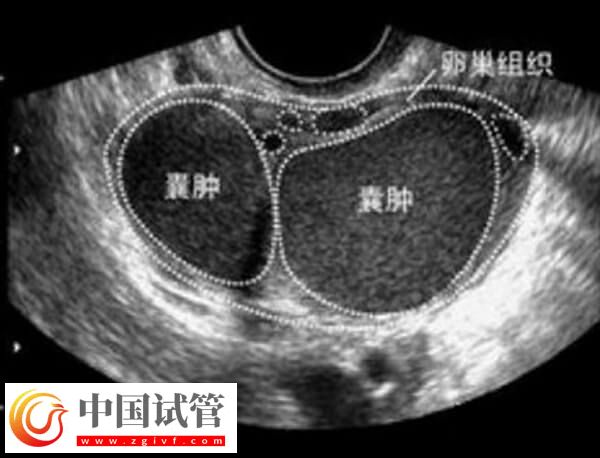

什么是卵巢巧克力囊肿

巧克力囊肿又称内膜异位症。它是由于月经来潮期间,子宫内膜组织向输卵管、盆腔或腹膜腔扩散而形成的一种赤褐色多房囊肿。卵巢因此形成大小不一的卵巢囊肿,通常伴随肚脐下部或骨盆区域疼痛以及月经不调等症状。